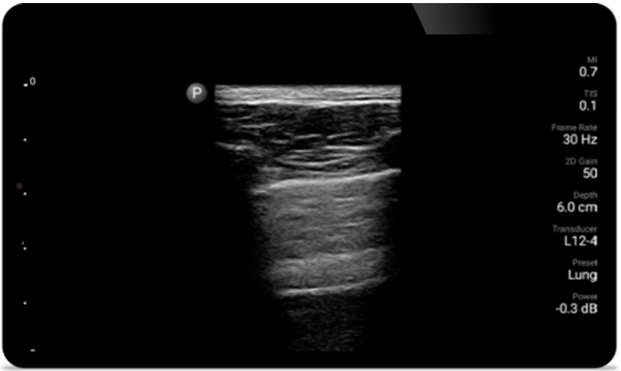

Breathe easier with

Lumify

Lumify can help assess patients faster and improve

accuracy when diagnosing common causes of

dyspnea and other lung conditions.

Lumify L12-4 broadband linear array transducer

• 12 to 4 MHz extended operating frequency range

• Aperture size: 34mm

• 2D, steerable color Doppler, M-mode, advancedXRES and multivariate harmonic imaging, SonoCT

• High resolution imaging for shallow applications: soft tissue, vascular, superficial, musculoskeletal and lung